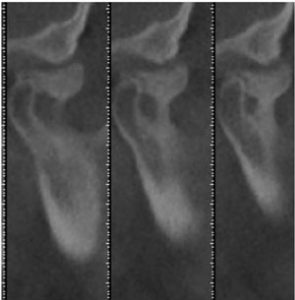

The CT scan of the right TM Joint produced a startling revelation. A large boney projection extended from the anterior condylar neck of the mandible superiorly, like a tree trunk, and mushroomed up to the opposing articular eminence. A 3-D projection showed the growth wrapped from posterior, to beneath, and even anterior to the articular eminence. This explained the inability to translate upon opening. A panoramic view also clearly showed the hard tissue pathological projection, which extended vertically beyond the height of the mandibular condyle, thus producing a resulting right side open bite. The diagnosis was quickly clarified through CBCT technology.